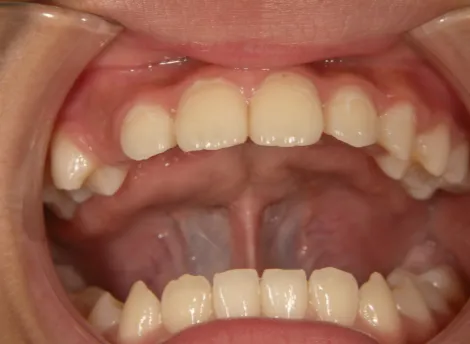

治療前①小2:8y1m 初診

| カウンセリング・診断結果 | 前歯が受け口になっていているため、適正な成長へ誘導するために前歯の咬み合わせの改善が必要なことを説明し、診断を希望されたので精密検査へ進みました。 精密検査の結果、骨格的には受け口傾向、下顎前歯の突出、上下ともアーチが小さく凸凹(叢生)が認められ、機能的には低位舌と口唇閉鎖不全があり、口元は上下唇とも突出していますがコンケーブになってないことがわかりました。 |